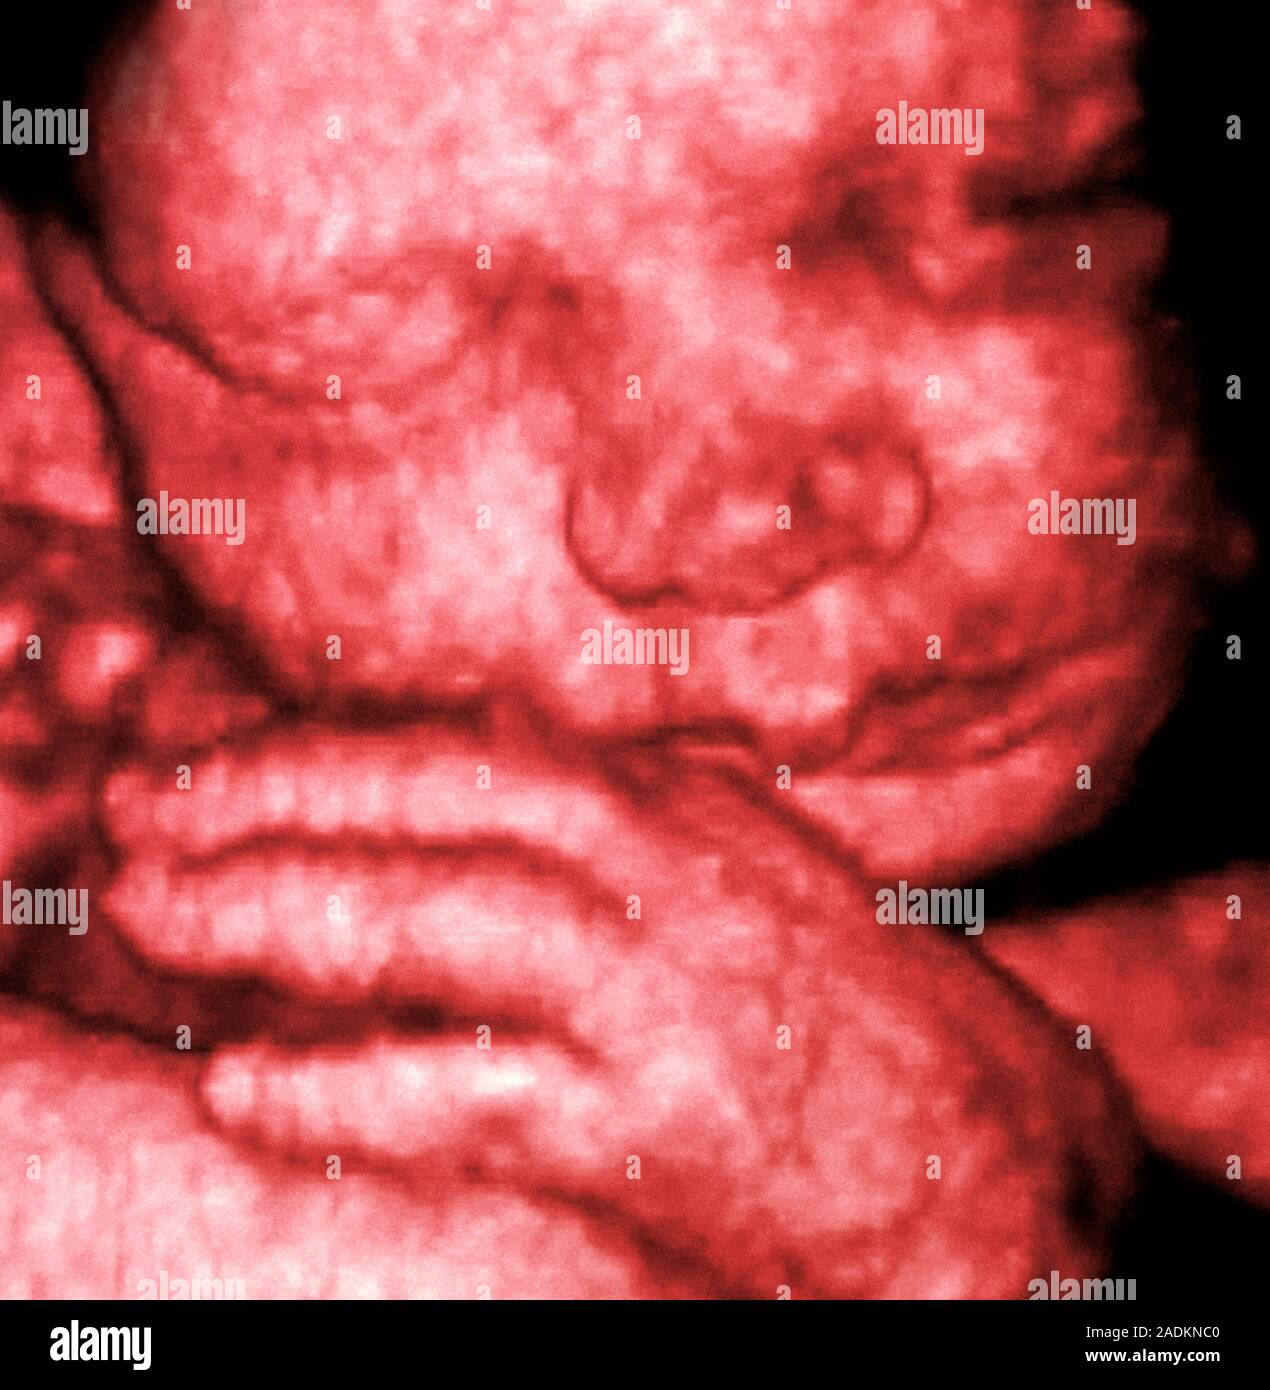

From www.alamy.com

3D foetal ultrasound. Coloured threedimensional (3D) ultrasound scan How Is Ultrasound Produced — how is ultrasound made? ultrasound waves are produced by a transducer, which can both emit ultrasound waves, as well as detect the ultrasound echoes reflected back. — ultrasound testing, also known as ultrasonography or sonography, is an imaging test that uses sound waves to. The source of the ultrasound wave is. ultrasound probes, called transducers,. How Is Ultrasound Produced.